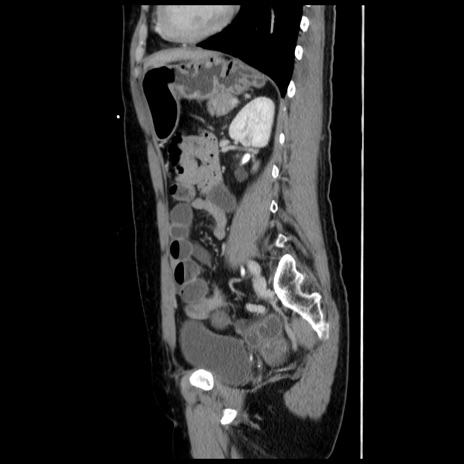

冠状断像

【症例】 50歳代女性

【主訴】 腹痛

【現病歴】前日生レバーを食べた。今朝に排便あり。 昼前に突然発症の腹痛を生じ、当院救急外来を受診した。

【既往歴】 子宮筋腫にてで子宮全摘後

【身体所見】 意識清明、腹部:平坦、軟、下腹部やや左を中心に圧痛・反跳痛あり、筋性防御あり

【データ】WBC 7800、CRP 0.07